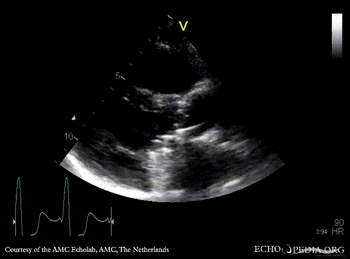

PLAX: mitral valve prosthesis and aortic valve prosthesis PLAX with Color Doppler